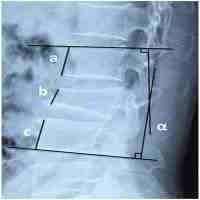

| Abstract | Background: Thoracolumbar spine fractures are common in the young healthy population. The most common causes of these fractures are high-energy traumas, traffic accidents or falls from heights. Fractures can be followed by neurological deficit, which is a direct consequence of the spinal cord and/or root(s) damage. Fractures are treated with surgical or nonsurgical methods. Transpedicular screw fixation is one of the methods of surgical treatment objective: The aim of the paper was to evaluate the results of the posterior short-segment transpedicular screw fixation in the treatment of unstable traumatic fractures of the thoracolumbar spine. Patient and methods: This retrospective study included fifty patients with the diagnosis of thoracolumbar traumatic spinal fracture without posttraumatic neurologic deficit in the neurosurgical department of Banha University Hospital. They were operated upon with posterior instrumentation between January 2006 and January 2012. Results: Fifty (28 males and 22 females) with age ranging between 16 and 66 years (mean 41.8, St.D. 11.3) were operated upon by posterior transpedicular screw fixation. According to the ASIA scoring system all patients were grade E. The mean kyphotic deformities measured preoperatively was 19.2 degrees (±5.5 degrees) and at within 12 months follow-up, was 8.0 degrees (±3.6 degrees). The mean mid-sagittal diameter improved from 9.2 mm (±3.1 mm) before surgery to 15.1 mm (±0.8 mm) at the 12 months follow-up visit. Conclusion: By applying the transpedicular screw fixation of the unstable fractures of the thoracolumbar spine, a stable fracture fixation can be achieved. This kind of fixation prevents secondary spine deformities. INTRODUCTION: The thoracolumbar region is generally accepted as that part of the spine formed by vertebrae from the 11 th thoracic to the 2 nd lumbar (1) . Spine fractures, especially fractures accompanied with the spinal cord injury, pose a difficult surgical, social and economic problem (2) . The three major trauma mechanisms for thoracolumbar spine fractures are rotation/translation, distraction, and compression (3,4) . Most thoracolumbar burst fractures are stable injuries that can be treated nonsurgically (5) . Regardless of neurologic deficits, unstable burst fracture that have retropulsed bone fragments compromising the canal requires surgical interventions such as decompression of neural structures, correction of spinal deformities and stabilization. (4,6) The success of the treatment depends on the initial medical treatment, radiological diagnosis, anatomical reduction, surgical decompression of the spinal canal (if needed) and surgical stabilization (7) . In cases of neurological damage, it is necessary to determine the exact grade of mobility impairment and of sensory functions (8) . The classification and gradation of neurological damage in patients with the fractures of thoracolumbar spine are determined according to the ASIA (American Spinal Injury Association) score (3,9) . This paper presents our experiences in the surgical treatment of thoraco-lumbar fractures by transpedicular screw fixation in patients who did not have any neurological damage. PATIENTS AND METHODS: Study design: This is a retrospective study of the data of fifty patients who were hospitalized with the diagnosis of traumatic thoracolumbar spinal fracture without posttraumatic neurologic deficit in the neurosurgical department of Banha University Hospital. There were operated upon with posterior short-segment instrumentation between January 2006 and January 2012. Preoperative assessment: Patients were clinically evaluated for type of injury, extent of Neurological deficit (ASIA grade) (Table 1) (8) . AnteriorPosterior (AP) and lateral Plain Radiographs, Magnetic Resonance Imaging (MRI) and 3D-Computerized Tomography (3D-CT) scan was carried out in all patients. The segmental kyphosis angle was measured on lateral radiographs as the angle between the superior endplate of the first uninvolved vertebra proximal to the affected segment and the first uninvolved vertebra distal to the affected segment. Based on computerized tomography and magnetic resonance images of the patients, we evaluated intracanal fragments, the presence of pedicle and laminar fractures, posterior ligamentous complex status and the presence of medullary edema. Table 1: Asia Impairment Scale A = Complete: No motor or sensory function is preserved in the sacral segments S4-5. B = Incomplete: Sensory but not motor function is preserved below the neurological level and includes the sacral segments S4-S5. C = Incomplete: Motor function is preserved below the neurological level, and more than half of key muscles below the neurological level have a muscle grade less than 3. D = Incomplete: Motor function is preserved below the neurological level, and at least half of key muscles below the neurological level have a muscle grade of 3 or more. E = Normal: motor and sensory function are normal Operative technique: Our surgical procedure was attempted to reach the retropulsed bone fragments through performing both laminectomy and minimal facetectomy. In prone position, we made a midline skin incision to expose the laminae 1 or 2 levels above and below the injured levels. We performed blunt dissection until the facet joints on both sides were seen. After routine laminectomy, we removed facet joints minimally to expose nerve root of both sides. Then, beneath the dural sac, we could push the retropulsed bone fragments down into the fractured vertebral body to their rightful position in the burst vertebral body. The manipulation was ought to be performed with great care to avoid damage to the neural structures. This was a crucial procedure to decompress the neural canal without removal of the retropulsed bone fragments. After the posterior decompression and bone fragment repositioning, the transverse processes, laminae of above and below level, and other posterior bony surfaces were decorticated for posterolateral fusion. Then, we carried out the classical short-segment pedicle screw instrumentation (transpedicular screw and rod instruments). Finally, we embedded sufficient amount of harvested bone fragments and artificial bone chips in the posterolateral sides of the column (posterolateral fusion) Follow up: The outcome was evaluated with (ASIA) (8) scale after three months, six months and one year following surgery. Plain x-Ray both anteroposterior and lateral views and 3D Computed Tomography were done postoperatively. The segmental kyphosis angle and the extent of collapse were measured on lateral radiographs at each visit. The presence of fusion was determined from two plain radiographs and was verified |